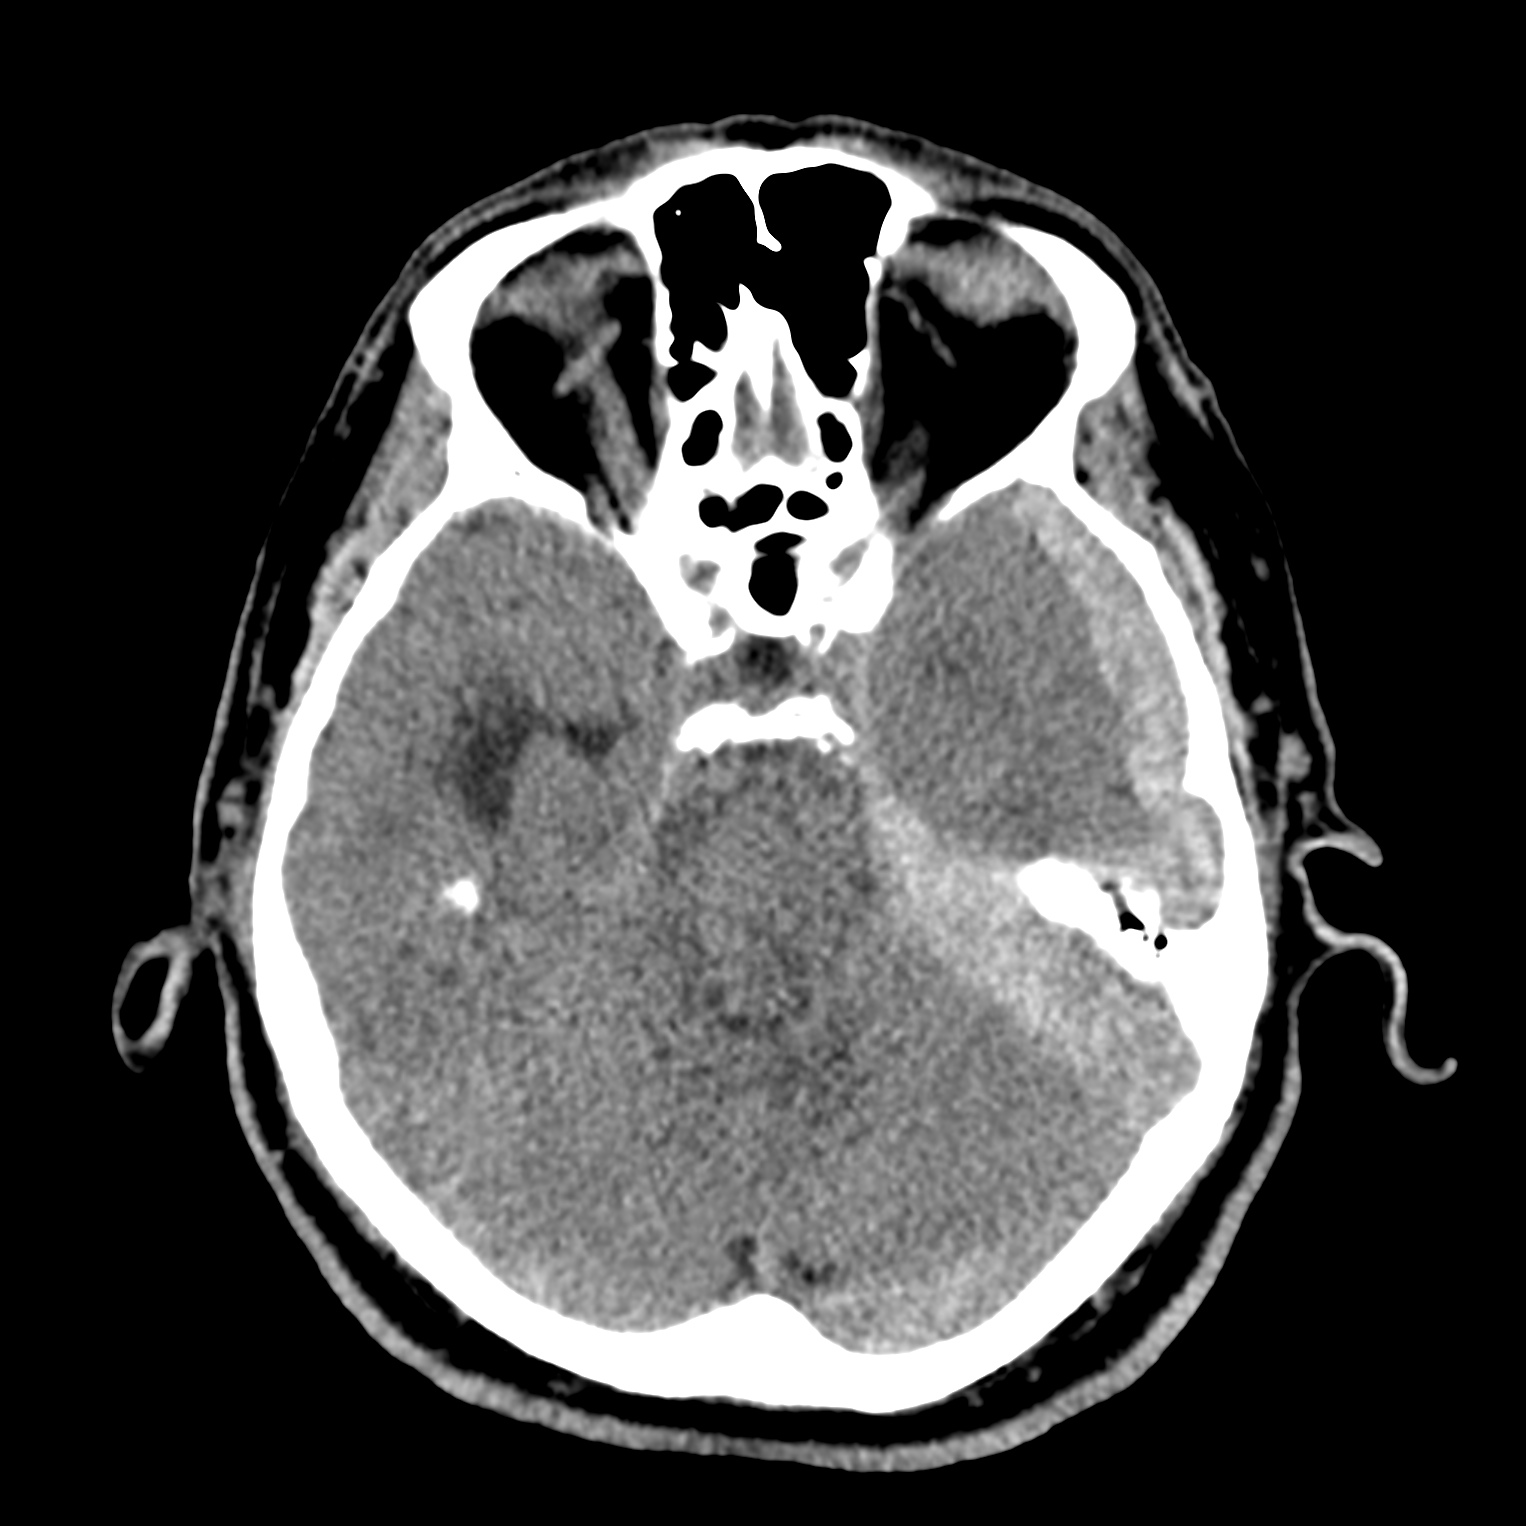

ちなみに画像診断とは、CTやMRIなどの画像を見て、正常か異常か、異常であればそれが何なのかを診断する仕事です。

Case courtesy of Andrew Dixon, Radiopaedia.org. From the case rID: 32383

医療従事者でなければ何のメリットも無いかもしれないのですが、実際の画像を自分でスクロールしながら学ぶことができるというのは、ものすごく大きなことだと思います。

さらに症例の解説を付け加えたら、読影能力アップのための強力なツールになるのではないかと期待しています。